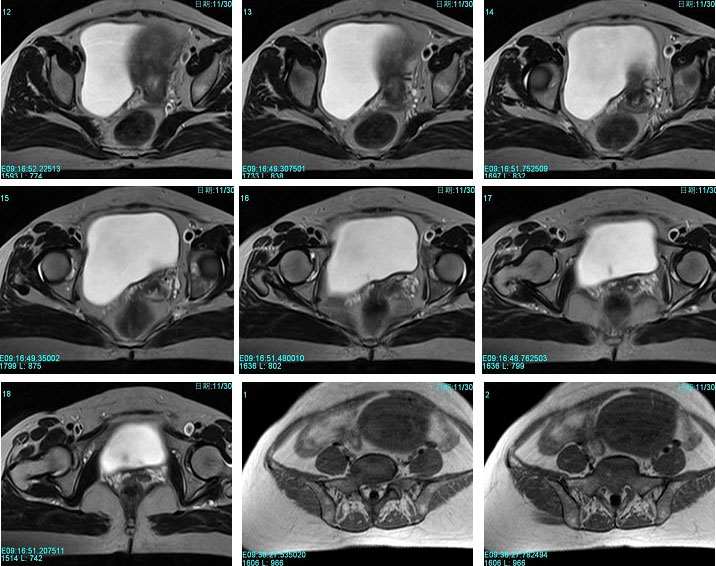

子宫恶性中胚叶混合瘤(癌肉瘤)

女性患者,52岁,月经量大,间断下腹痛一年余。多考虑:1:子宫前壁肌瘤。2:子宫内膜癌可能性大。已取活检,病理结果过几天出来。各位高手先讨论讨论。

子宫内膜太厚,结合带不完整,考虑内膜癌,建议刮宫病检。

宫内膜太厚,结合带不完整,考虑内膜癌,建议刮宫病检。

术后病理结果出来啦!